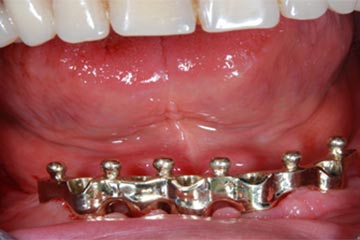

Protesi totale con mesostruttura avvitata su 5 impianti in un paziente edentulo